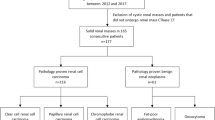

Seventy patients with small renal tumors treated with robot-assisted partial nephrectomy were included. Patients were divided into two groups according to the presence of APF. We extracted 15 image features from unenhanced CT and contrast-enhanced CT corresponding to first-order and second-order Haralick textural features. Predictors of APF were evaluated by univariable and multivariable analysis. Receiver operating characteristic (ROC) analysis was performed and the area under the ROC curve (AUC) to predict APF was calculated for the independent predictors.

APF was observed in 26 patients (37%). We identified entropy (p = 0.01), sum entropy (p = 0.02) and difference entropy (p = 0.05) as significant independent predictors of APF. In the portal phase, we identified correlation (p = 0.03), inverse difference moment (p = 0.01), sum entropy (p = 0.02), entropy (p = 0.01), difference variance (p = 0.04) and difference entropy (p = 0.02) as significant independent predictors of APF. Combining these parameters yielded to an ROC-AUC of 0.82 (95% CI 0.65–0.86).